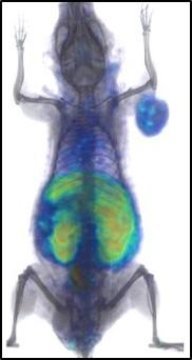

They next sought to verify this effect in animals. The researchers treated mice that had implanted human lung tumors with a single dose of atezolizumab — a drug that fights cancer by binding to PD-L1 — and waited 24 hours, allowing the checkpoint inhibitor to bind to PD-L1. They followed this treatment with the radiolabeled peptide and PET imaging.

When the mice in the experimental group receiving atezolizumab were compared to controls that received only a saline injection, the researchers found a 77 percent reduction in unoccupied PD-L1 levels in the tumor, indicating that treatment reached many of the PD-L1 proteins.

“The remaining areas indicate parts of the tumor that the immunotherapy didn’t reach,” says Nimmagadda, who is a member of the Institute for Basic Biomedical Sciences at the Johns Hopkins University School of Medicine. “In human patients, this could give us some insight about how to optimize further treatments by increasing the dose or substituting other drugs or therapies more quickly.”